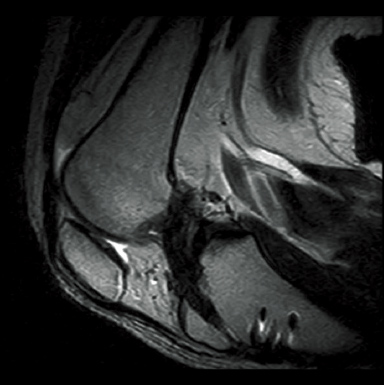

FatSat-PDWI

T2WI